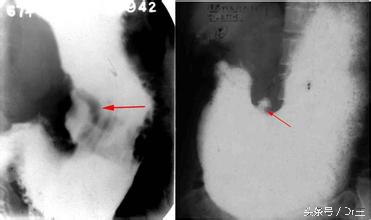

消化性溃疡疾病是一种慢性发炎的情形,它包括了十二指肠溃疡及胃溃疡、胃食道逆流疾病、麦式憩室疾病等。我们晓得胃酸是非常具有破坏性的胃分泌液,而我们胃黏膜经过数种防卫机转以及保护,如此才能避免溃疡的发生,正常的胃幽门的功能和胃排空以降低胃酸分泌的负回馈机制是非常重要的,这些与某些物质有关,譬如前列腺素、一氧化氮、一些特殊蛋白质等来协调其功能,因此以上这些物质产量降低,将会使的分泌正常的胃酸来伤害自己的黏膜,进一步导致所谓的黏膜破皮最后变成溃疡。其他如幽门螺旋杆菌的感染以及长期使用一些消炎药,譬如非类固醇抗发炎药物等,都会降低胃黏膜的保护最后造成胃溃疡或其他消化性溃疡的疾病。

一般说来,肠胃内科医师会根据病史、上消化道内视镜、幽门螺旋杆菌的诊断等等,来确定其罹患的疾病是属于哪一种,最后会依照诊断的结果施予不同的药物,一般有患者所熟悉的制酸剂、H2受主拮抗剂、氢离子帮浦阻断剂(PPIs)、misoprostol等,如果证据显示有胃幽门螺旋杆菌感染,则会使用幽门螺旋杆菌根除疗法,包括数种抗生素的交互使用,以增加根除这类溃疡性疾病的机会。